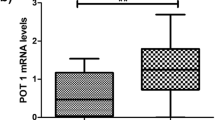

BCR::ABL1-mediated effect on TERC, TERT, and DKC1 expression of telomerase components during CML progression. a–c The TERC (n = 54), TERT (n = 33), and DKC1 (n = 42) expression levels normalized to B2M and GUSB measured with qPCR **p < 0.01(non-parametric Student’s t test and Mann–Whitney post-test). d PCR ELISA measurement of telomerase activity, n = 10 (non-parametric student t test and Mann–Whitney post-test). e–g Correlation between BCR::ABL1 and TERC, TERT or DKC1 expression level, respectively (Pearson’s (r)) p < 0.05

Next, we checked the transcriptional activity of the DKC1 gene—nucleolar protein, which is responsible for maintaining TERC stability by interacting with H/ACA consensus sequence in TERC. The conducted comparison between the expression of the DKC1 gene in two groups of CML CD34+ showed a statistically significant increase (2.1-fold) of DKC1 expression in CML-BP cells in comparison with CML-CP cells (Fig. 2c). Additional correlation analysis conducted on CML CD34+ cells showed a statistically significant correlation between DKC1 expression and the BCR::ABL1 gene (r = 0.68 p < 0.0001) (Fig. 2g), and, interestingly, such significance was not found for TERC or TERT genes (Fig. 2e, f). Moreover, there was no significant difference in telomerase activity between CML-CP and CML-BC cells (Fig. 2d).

Comparative analysis of the expression profile of genes of the telomere complex, such as TRF1, TRF2, POT1, RAP1, TTP1, TNKS1, and TNKS2 in CML-CP and CML-BP cells, showed a statistically significant increase in the expression of two genes: TNKS1 and RAP1 in CML-BP cells (p < 0.01) (Fig. 3a). The average level of RAP1 expression was 1.4-fold higher for CML-BP cells and 1.72-fold higher for TKNS1 in relation to CML-CP cells, respectively. A comparison between the expression of different genes of the shelterin complex and the level of BCR::ABL1 transcription showed statistically significant correlations with the following genes: RAP1 (p = 0.0006), TRF2 (p = 0.003), TPP1 (p = 0.01), TNKS1 (p < 0.0001) and TNKS2 (p = 0.017) (Fig. 3b).

CML phase and BCR::ABL1 expression-mediated changes in the expression of TRF1 (n = 52), TRF2 (n = 53), POT1 (n = 52), RAP1 (n = 48), TINF2 (n = 49), TPP1 (n = 49), TNKS1 (n = 51) and TNKS2 (n = 49) genes. a Comparison of RAP1, POT1, TRF1, TRF2, TPP1, TNKS1 and TNKS2 gene expression between CML-CP and CML-BP patients. The gene expression was normalized to B2M and GUSB and measured with qPCR, **p < 0.01 (non-parametric student t test and Mann–Whitney post-test). b Correlation between BCR::ABL1 and TRF1, TRF2, POT, RAP1, TINF2, TPP1, TNKS1 or TNKS2 expression levels (Pearson’s (r), p < 0.05)